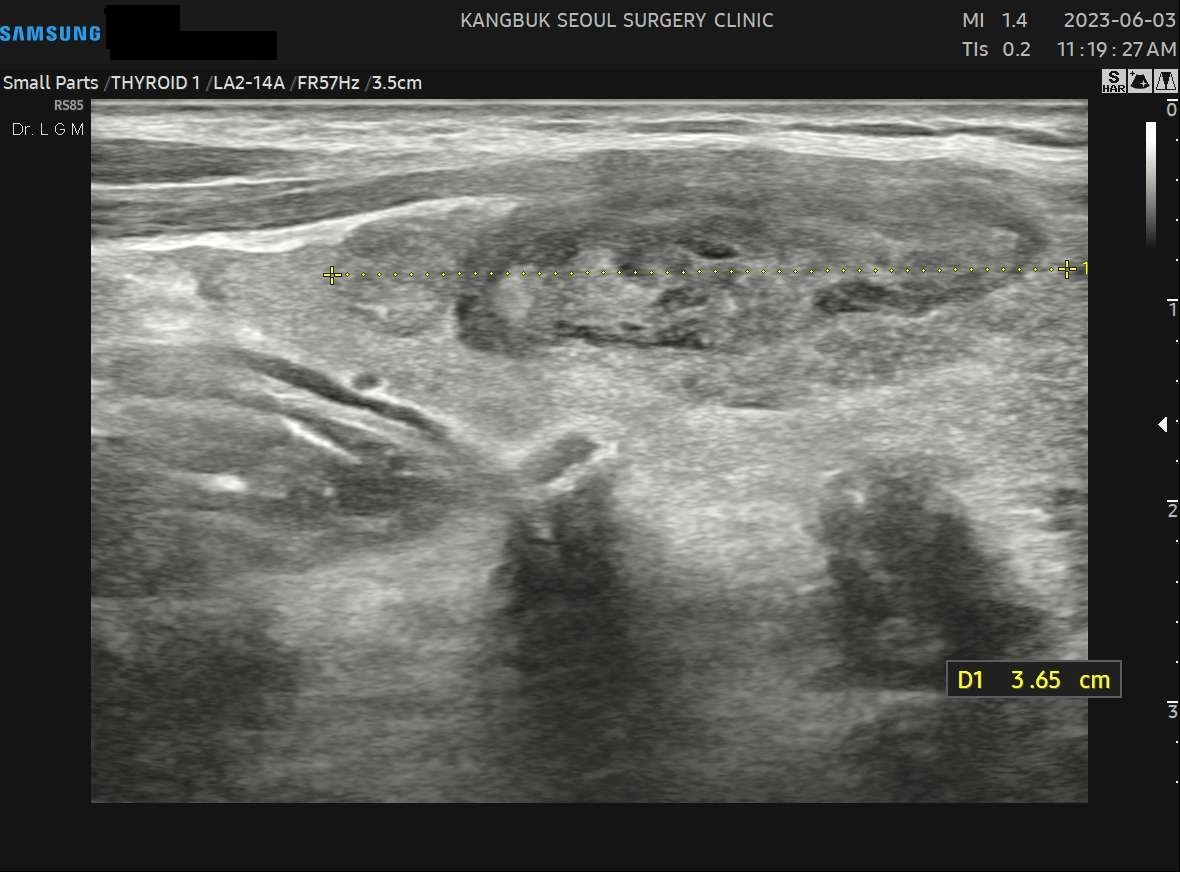

사례 1

수술 3개월 후(3.65cm)